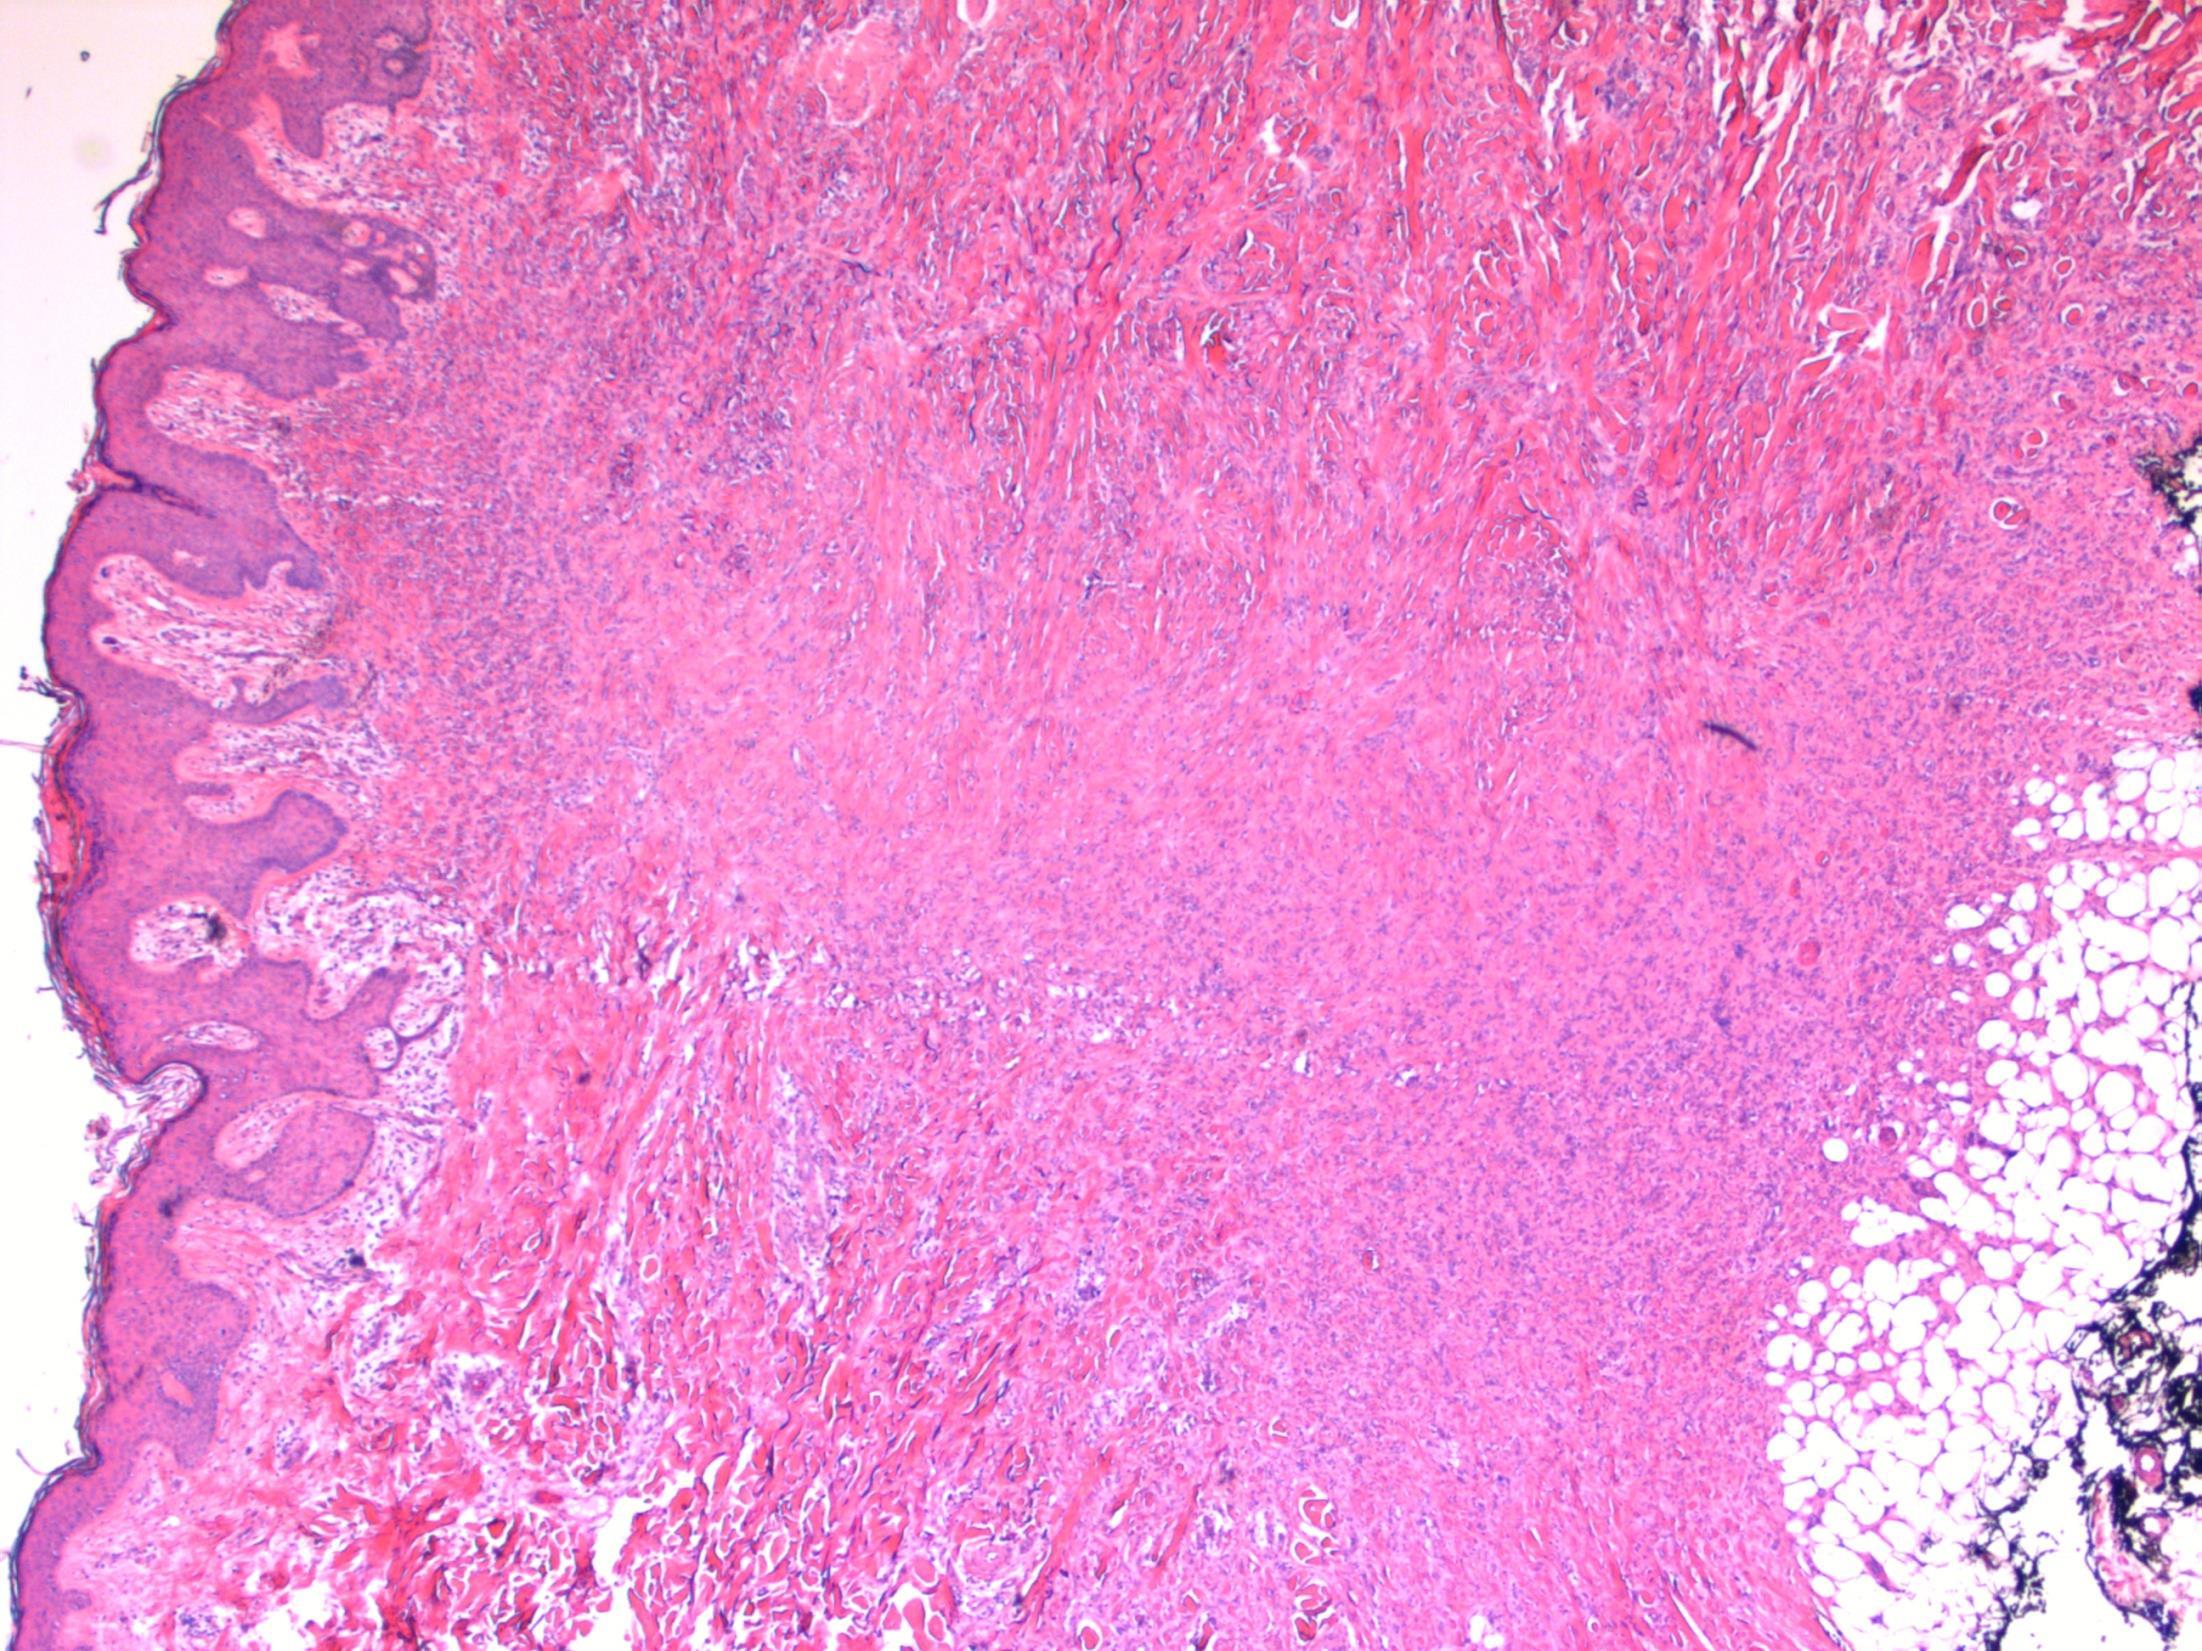

Dermatofibroma

Description: Pseudoepitheliomatous hyperplasia of the overlying epidermis. In dermis –short fascicles of spindle cells with individual collagen bundles surrounded by lesional cells at the periphery; giant cells, macrophages, inflammatory cells. Focal extension to subcutis.

Diagnosis: dermatofibroma

Plan: Correlate with clinical history: Often appear after a minor injury to the skin, vaccination or insect bite. Check other blocks for excision status.

Comments:

Many variants (aneurysmal, cellular, atypical)

Benign behaviour

Extremities commonly affected – like in this case. Local recurrence is rare, even with involved margins